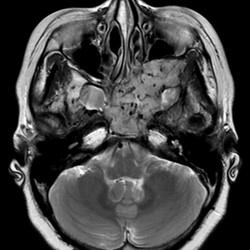

MRI

腫瘤はT2強調像高信号、T1強調像軽度高信号、拡散強調像軽度高信号(ADCは上昇)で、造影効果を認める。腫瘤内部および辺縁にはflow voidと思われる線状~点状の無信号域が多発している。